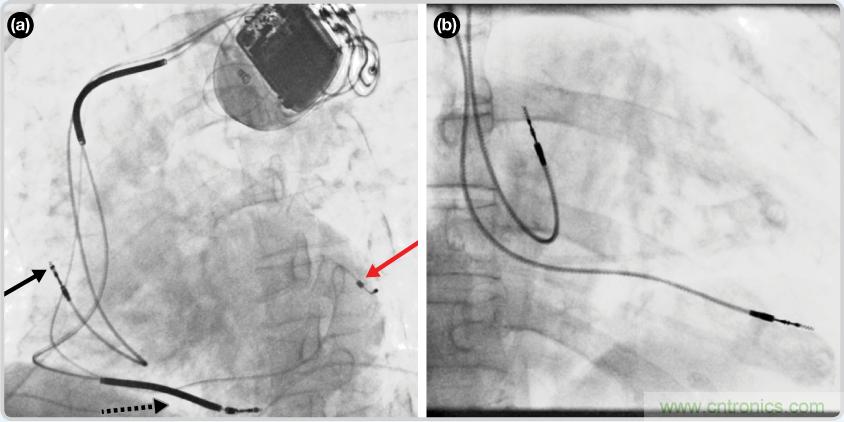

CRT器件在圖4(a)中的透視圖像中可以看見。醫(yī)師就是利用這種影像來放置導(dǎo)聯(lián)線的。對于非專業(yè)人士來說,這種影像是很難解讀的??梢钥吹叫呐K淡淡的輪廓——這是搏動中的心臟的靜態(tài)視圖。起搏器位于右心房上,心臟頂點(diǎn)指向右下方。在這個典型的導(dǎo)聯(lián)線放置實(shí)例中,黑色箭頭指向右心房導(dǎo)聯(lián)線。虛線黑色箭頭指向右心室導(dǎo)聯(lián)線。紅色箭頭標(biāo)示的導(dǎo)聯(lián)線只能看到一部分,這是左心室導(dǎo)聯(lián)線(紅箭頭指向電極尖端)。圖4(b)展示的是雙腔起搏器的典型導(dǎo)聯(lián)線放置透視圖像。右心房導(dǎo)聯(lián)線指向上方,置于右心房中。右心室導(dǎo)聯(lián)線則位于右心室頂部。

圖4. 起搏器導(dǎo)聯(lián)線放置的透視圖像3 (a). 單腔起搏器;(b).雙腔起搏器